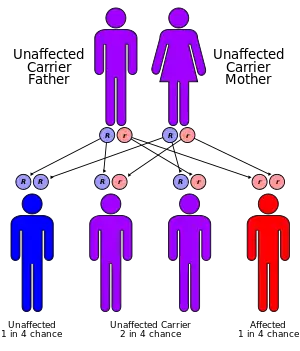

It is a rare autosomal recessive disorder.[4]

The MTTP gene provides instructions for making a protein called microsomal triglyceride transfer protein, which is essential for creating beta-lipoproteins.[12] These lipoproteins are both necessary for the absorption of fats, cholesterol, and fat-soluble vitamins from the diet and necessary for the efficient transport of these substances in the bloodstream.[13] Most of the mutations in this gene lead to the production of an abnormally short microsomal triglyceride transfer protein, which prevents the normal creation of beta-lipoproteins in the body.[14] MTTP-associated mutations are inherited in an autosomal recessive pattern, which means both copies of the gene must be faulty to produce the disease.[14]

The initial workup of Abetalipoproteinemia typically consists of stool sampling, a blood smear, and a fasting lipid panel, though these tests are not confirmatory.[16] As the disease is rare, though a genetics test is necessary for diagnosis, it is generally not done initially. However, prenatal testing may be available for pregnancies identified to be at an increased risk (if both parents are unaffected carrier or one parent is affected and the other in a carrier).